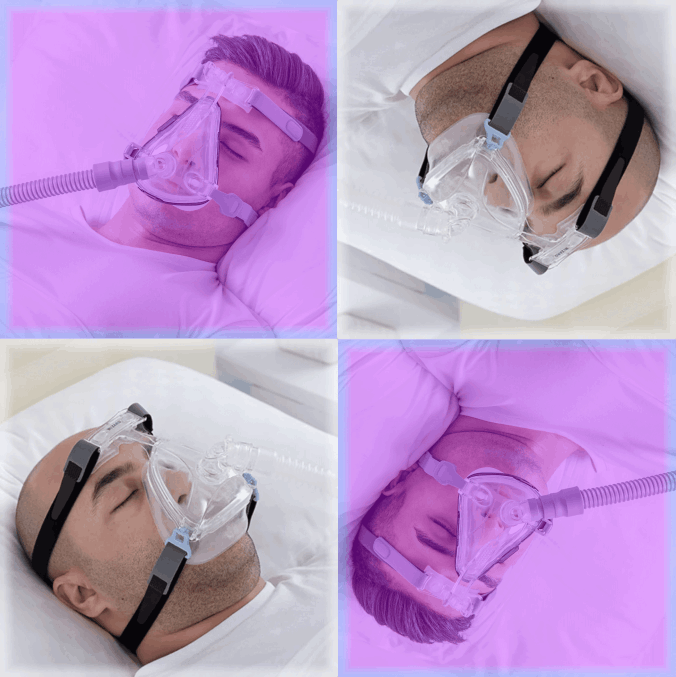

Como Sociedad Chilena de Medicina del Sueño tenemos una gran noticia, comienza el programa “Dale un nuevo aire a tu CPAP”, un programa para pacientes con sd. de apnea obstructiva del sueño.

Las apneas del sueño son una condición médica muy frecuente que afecta a 1 de cada 3 adultos e involucra la presencia de frecuentes pausas respiratorias mientras se duerme.

Padecer apneas del sueño se asocia a un aumento de frecuencia de condiciones como la diabetes, obesidad, hipertensión, infartos cardíacos, accidentes vasculares y deterioro cognitivo.

El tratamiento más efectivo, especialmente en el caso de las apneas más graves, es el uso de un equipo que ayuda a normalizar la

respiración en la noche llamado CPAP

CPAP significa Presión Aérea Positiva Continua, es decir, que el mismo aire que se respira (sin oxígeno adicional) se empuja a cierta presión de manera constante para generar un colchón de aire en las vías respiratorias y evitar que se cierren, logrando normalizar la respiración al dormir.

Si por alguna razón decidiste renovar tu equipo, dejaste de usarlo, o un familiar ya no lo usará, alguien más, de escasos recursos, podría beneficiarse de tu ayuda. Considera la posibilidad de donarlo y haz una diferencia.

Acércate a tu médico tratante o escríbenos a secretaria@sochimes.cl.